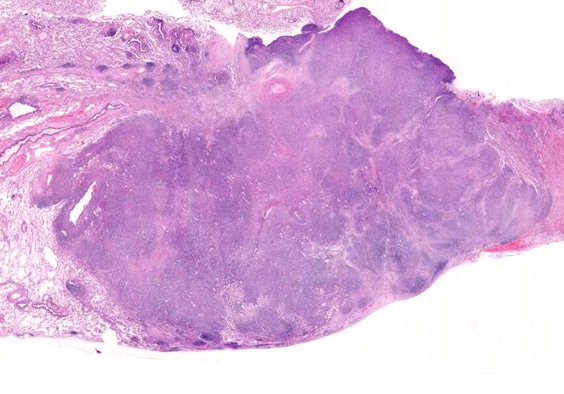

EBUS-GS(ガイドシース併用気管支腔内超音波断層法)による肺生検組織病理所見.

血管周囲性に大型類円形核や不整形核をもつ腫瘍細胞がシート状密に浸潤増殖している. Mitosisが多く認められる.細血管閉塞や破壊の所見がある.

間質にもシート状の腫瘍細胞浸潤がある. 大小 pleomorphicな傾向.(A, B). necrosisが認められる(C). 細気管支上皮直下まで密な浸潤あり, 小型リンパ球が混在している.(D)

血管中心性浸潤. 障害された血管内に血栓が形成されている.CD20陽性細胞がシート状密に浸潤, CD3陽性T細胞が多く混在している. EBER-ISH陽性 EBV感染細胞が多数認められ, >50 hpf, 定義より Grade3となる. 陽性細胞のサイズは大小さまざまであることに注意. Lymphomatoid granulomatosisの病態(WHO5thの診断では EBV-positive diffuse large B-cell lymphomaになる)をとっているが MTX-associated LPDの一型とするべき症例かもしれません.